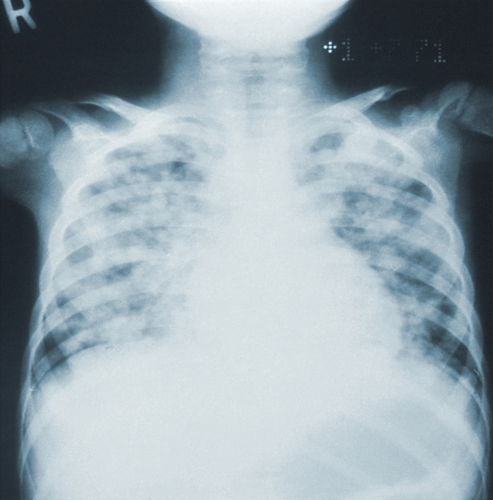

만성 기관지염은 가래와 기침이 계속되는 질환으로, 2년 연속으로 1년에 3개월 이상 가래가 있는 경우 진단됩니다. 그러나 다른 폐 질환이나 기도 질환에서도 가래를 동반한 기침이 오랫동안 지속될 수 있으므로 만성 기관지염을 진단하기 위해서는 다른 질환을 제외하는 검사를 해야 합니다.폐렴과 만성 기관지염은 폐에 영향을 주는 질환으로, 질병의 발생 기전 및 경과가 유사하여 한데 묶여 "만성 폐쇄성 폐 질환"이라고도 합니다.

따라서 폐렴과 만성 기관지염을 예방하고 조기에 치료하는 것이 중요합니다.폐렴은 주로 세균이나 바이러스 등 감염 요인에 의해 발생하며, 알레르기 반응, 방사선, 심각한 미세먼지 등에 의해 염증이 발생되어 발생할 수 있습니다. 다양한 원인이 있지만, 주로 감염으로 인한 경우가 많습니다.표에 내용을 정리하여 가독성 있게 작성할 수 있으며, 이를 위해태그를 사용해 표를 만들어 주세요. 텍스트는 폐렴과 전염에 관련된 내용으로 채워주세요. 폐렴 초기증상과 감기 전염 가능성에 대한 글을 마치며, 가족이나 지인 중 면역력이 약한 사람이 감기 증상을 보인다면 폐렴인지 주의 깊게 살펴보는 것이 중요합니다.

| 질환 | 원인 | 전파 방법 | 증상 | 예방 | 치료 |

| 폐렴 | 세균, 바이러스, 균류 | 호흡기 분비물 전파 | 호흡곤란, 가열, 기침 | 예방주사, 손 씻기, 예방접종 | 약물 요법, 휴식, 수액 |

| 만성 기관지염 | 환경, 유전적 요인 | 접촉, 에어로졸 전파 | 가래, 지속적인 기침 | 환경 개선, 약물 예방 | 약물 치료, 물리 치료 |